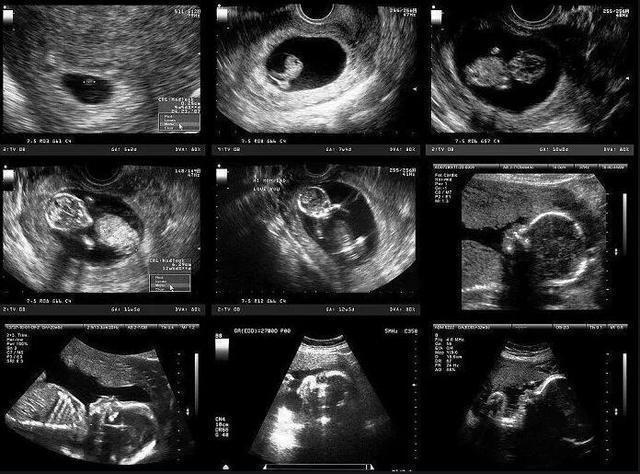

孕期最后一个月,孕妇需要注意什么问题?“三做二不做”要遵循三做:1.产检必须做孕37周开始,孕妇每周都得产检,可能是基础的检查,可能是尴尬的内检,不管是哪种检查,都不能错过。最好在医生要求的时间内检查。如果期间出现异常,比如胎动异常或者宫缩太过频繁,也要及时就医。2.劳逸要结合都说孕晚期多走有助于顺产。但是到底走多少合适,是越多越好吗?之前看到一个报道,为了利于顺产,有个孕妇每天步行1万步,谁知走了没几天就出现了早产迹象,据医生解释,是走的太多引起的。所以说,走路并不是越多越好,具体还要看孕妇的自身情况。如果身体健康,没有异常,可以多走几步;如果累了、倦了,或者出现假性宫缩,都需要及时休息。总而言之,就是要“劳逸结合”,别过度!